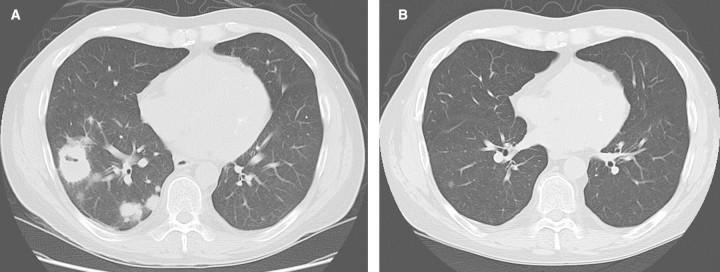

Antineutrophil cytoplasmic antibodies-associated vasculitis (AAV) is a well-described cause of multiple organ involvement including rapidly progressive pauci-immune crescentic glomerulonephritis. Kidney transplantation (KTx) is considered the treatment of choice in patients with end-stage renal disease (ESRD) due to AAV. Patient and graft survival in AAV after KTx is favourable and comparable with other non-diabetic causes of ESRD. While relapse of AAV is high in dialysis patients (up to 50%), it decreases after KTx (8.6-22.2%). Yet, relapse may occur at any time after KTx and transplant involvement has been documented in at least 25 cases. Therapeutic guidelines for the management of AAV after KTx do not exist and clinical management is a controversial discussion. We present two unusual cases of young males with smouldering AAV who recently underwent KTx at our hospital. Case 1 experienced repeated relapses after KTx and was finally successfully treated with rituximab. Case 2 received rituximab pre-emptively before living kidney donation and remained free of flairs. Prompted by theses two cases, we reviewed the literature focusing on the right point of time for transplantation, risk assessment, role of antineutrophil cytoplasmic antibodies, clinical presentation of flairs and immunosuppression in smouldering Wegener's granulomatosis (WG) and in relapse, including individualized treatment with rituximab.

抗中性粒细胞胞浆抗体相关性血管炎(AAV)是一种已被充分描述的可导致多器官受累的病因,包括快速进展性寡免疫性新月体性肾小球肾炎。肾移植(KTx)被认为是因AAV导致终末期肾病(ESRD)患者的首选治疗方法。AAV患者肾移植后的患者及移植物存活率良好,与ESRD的其他非糖尿病病因相当。虽然AAV在透析患者中的复发率很高(高达50%),但肾移植后复发率会降低(8.6%-22.2%)。然而,肾移植后复发可能在任何时间发生,并且至少有25例记录了移植肾受累情况。目前不存在肾移植后AAV管理的治疗指南,临床管理存在争议。我们报告了两例患有隐匿性AAV的年轻男性的不寻常病例,他们最近在我院接受了肾移植。病例1肾移植后经历了多次复发,最终用利妥昔单抗成功治疗。病例2在活体肾捐献前预防性使用了利妥昔单抗,且未出现病情复发。受这两个病例的启发,我们回顾了文献,重点关注移植的合适时机、风险评估、抗中性粒细胞胞浆抗体的作用、隐匿性韦格纳肉芽肿(WG)及复发时病情复发的临床表现和免疫抑制,包括利妥昔单抗的个体化治疗。